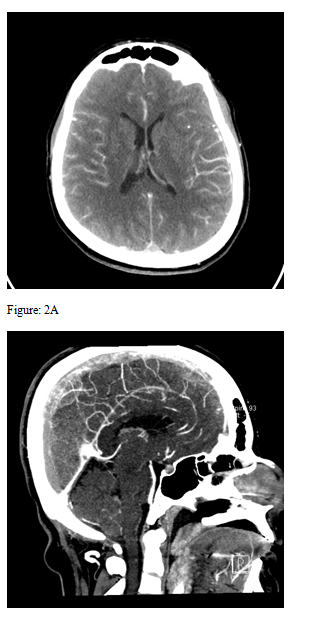

The “Empty Delta Sign” (Figure 2)

The “Empty Delta Sign” seen in (A) with contrast-enhanced CT scan is a central region lacking contrast in the posterior superior sagittal sinus (B).

Figure 2B: The “Empty Delta Sign” seen in (A) with contrast-enhanced CT scan is a central region lacking contrast in the posterior superior sagittal sinus (B).

seen with contrast-enhanced CT scan is a triangular ring of enhancement with a central region lacking contrast in the posterior superior sagittal sinus [4]. Emergency physicians, who strongly suspect CVST should obtain non-contrast CT, followed by contrast enhanced CT, and finally MRI/MRV (Figure 3).

MRV showing a dense area in the superior sagittal sinus.

Figure 3: MRV showing a dense area in the superior sagittal sinus.